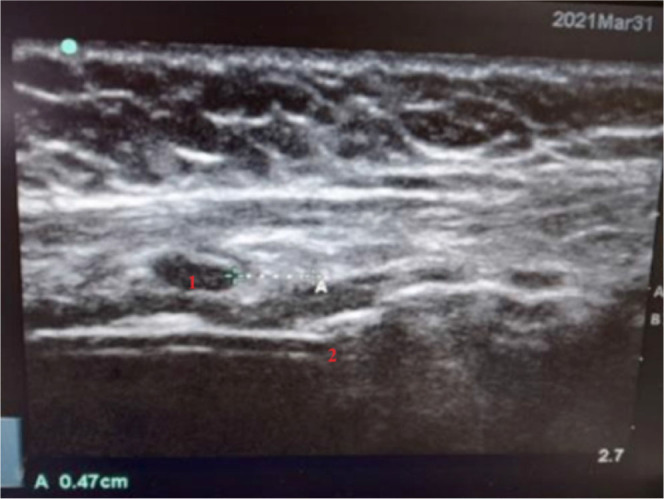

Aim of the study: Our primary objective was to determine whether ultrasound guided visualisation of proximal end of endotracheal tube cuff is better when compared to conventional method in optimal positioning of tube tip. The secondary objective was to find the optimal endotracheal tube position at the level of incisors in adult Indian population.

Materials and methods: There were 25 patients each in the conventional group and the ultrasound group. Conventional method includes auscultation and end tidal capnography. In the ultrasound group the upper end of the endotracheal tube cuff was positioned with an intent to provide 4 cm distance from the tube tip to the carina. X ray was used in both groups for confirmation of tip position and comparison between the two groups. Further repositioning of the tube was done if indicated and the mean length of the tube at incisors was then measured.